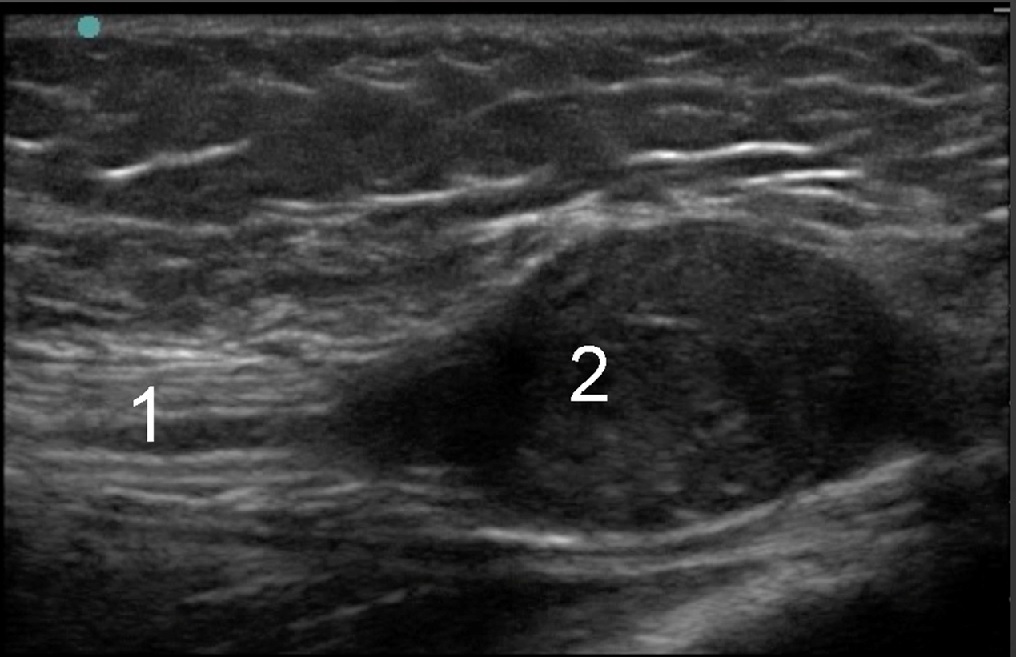

Medial Ankle Schwannoma Image

Normal Nerve

Schwannoma